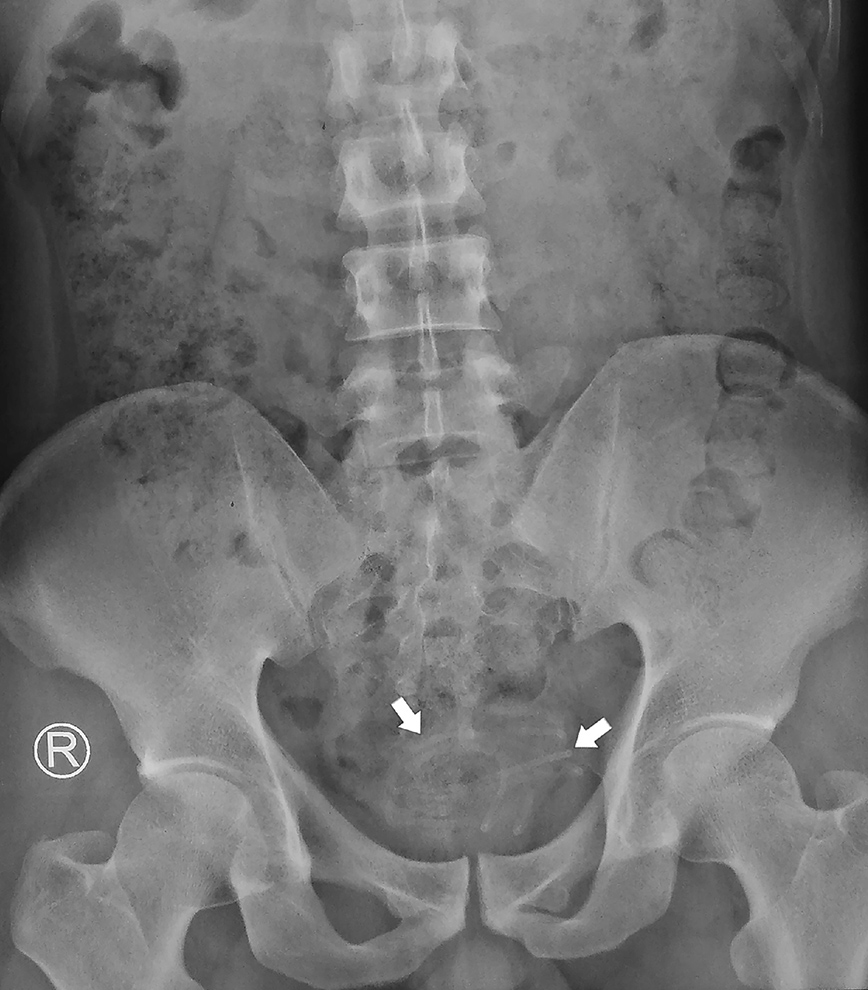

Το έκανε αυτό 3-5 φορές την εβδομάδα για «σεξουαλική ευχαρίστηση και ικανοποίηση», όπως αναφέρει η New York Post. Αλλά αυτή τη φορά, ο άνδρας δεν μπορούσε να βγάλει το καλώδιο όταν αυτό σφηνώθηκε στην ουροδόχο κύστη του, το οποίο ήταν «ορατό και γρήγορα εντοπίστηκε» από την ομάδα.

Το σύρμα ήταν τυλιγμένο και ευτυχώς δεν είχε προσκολληθεί στο τοίχωμα της ουροδόχου κύστης και η εξαγωγή του έγινε με λαβίδα σύλληψης. Διαπιστώθηκε ότι το καλώδιο των ακουστικών είχε μέγεθος 78 εκατοστών. Ο ασθενής πήρε εξιτήριο την επόμενη ημέρα.